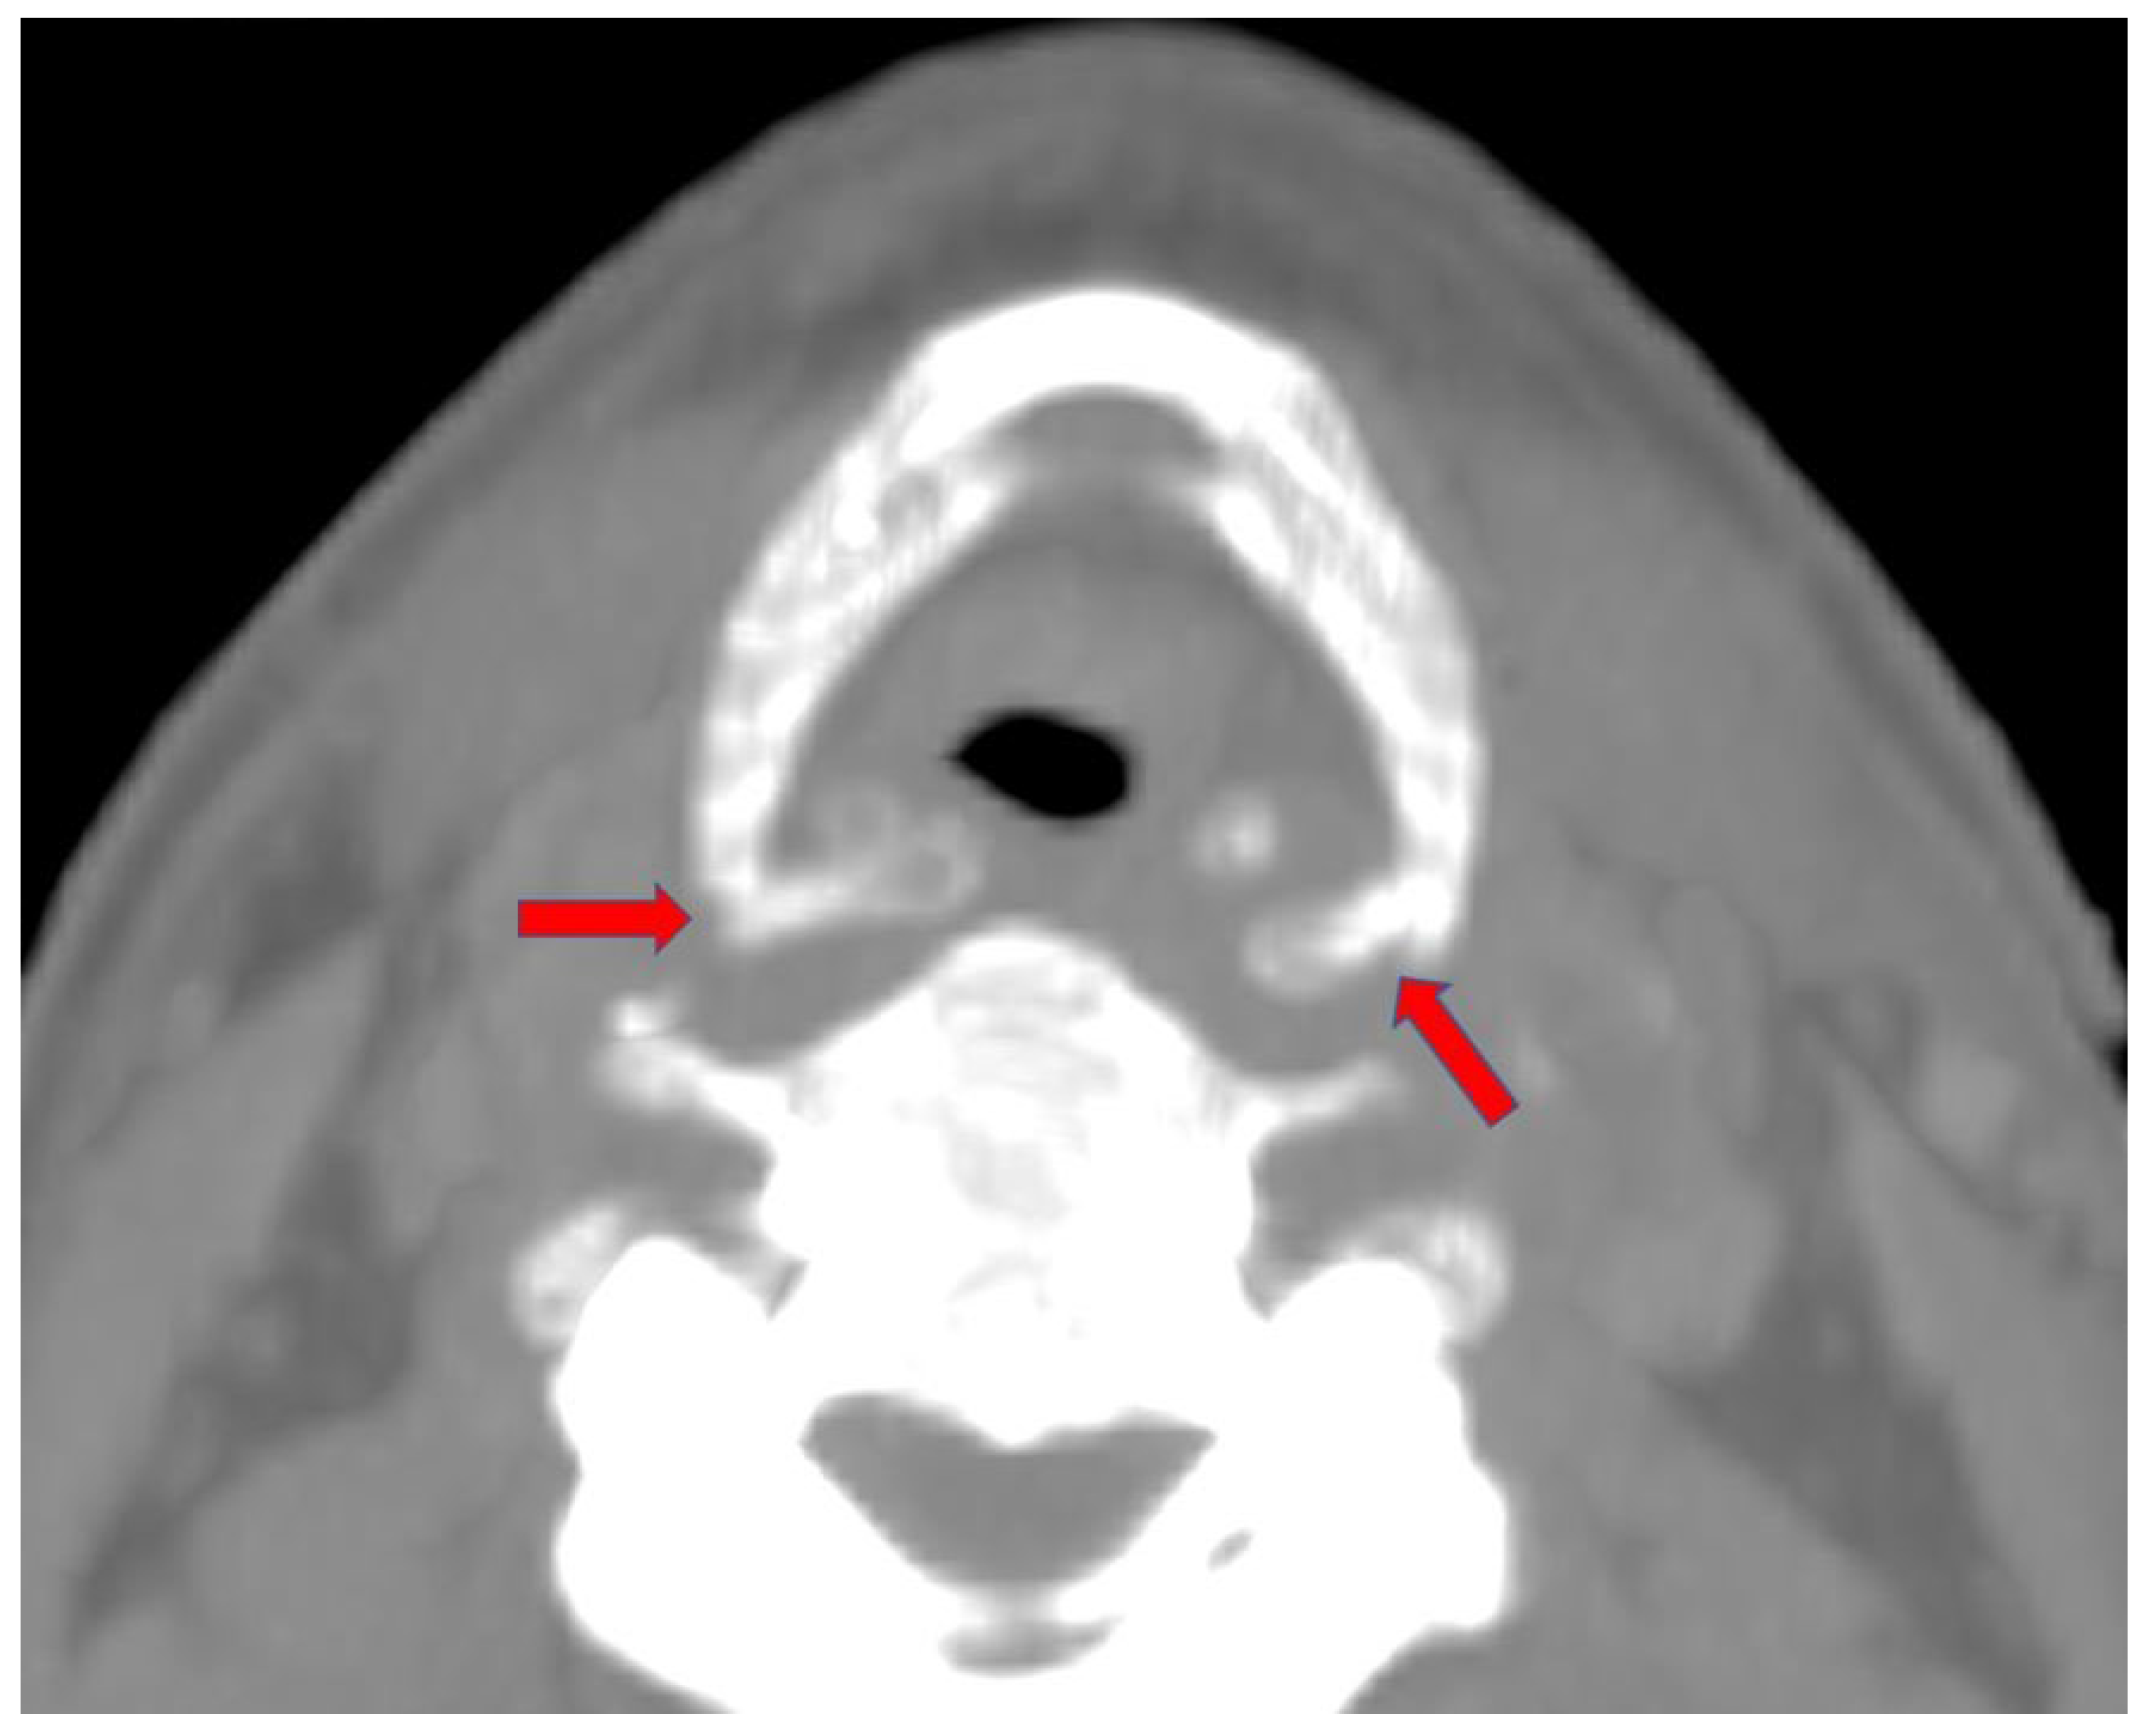

2. Case Report